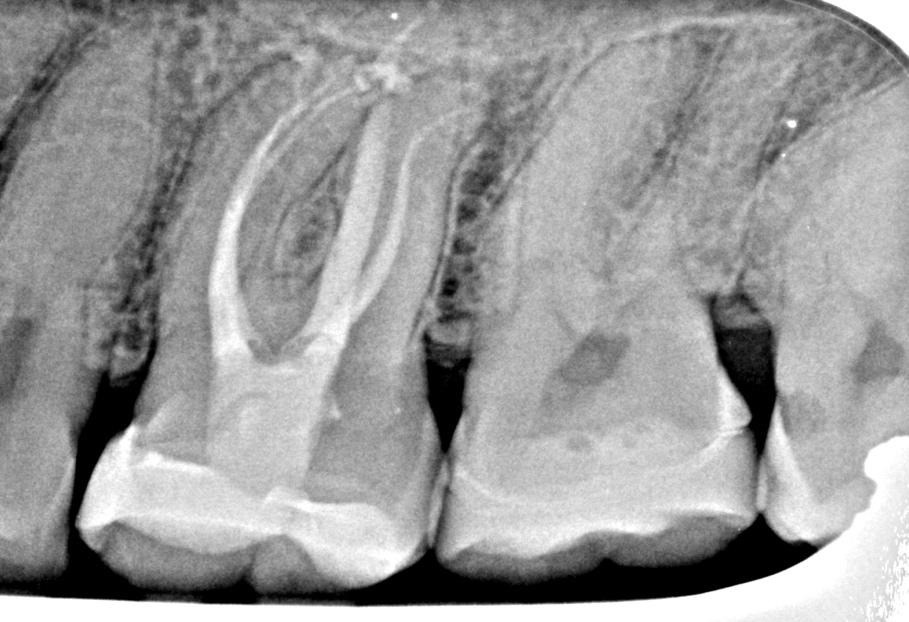

Conservative Access and Root Canal Preparation on a Curvy Molar with 4 Portals of Entry and 5 Portals of Exit

Hybrid sequence of MiniKut 1503, TS 1802, TS 2004 in mb1, mb2 and db. The palatal was finished with a VDW Rotate 3004. This sequence was chosen to suit the narrow-calcified canals. It enabled slow and gradual enlargement of the canals which reduce the chance of the file breakage especially in the distobuccal canal with the ‘s’ shaped curve.

Obturated with

Hydraulic condensation with TotalFill BC sealer Hiflow.